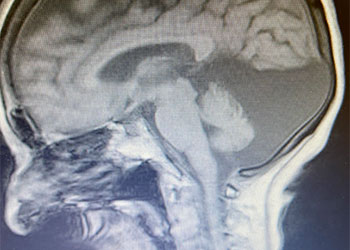

Endovascular:

Hydrocephalus and Brainstem Tumor

Author: Jonathan L. Brisman M.D., F.A.C.S., Read More!